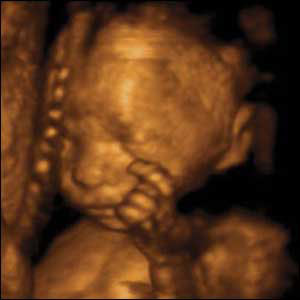

L'ottavo mese di gravidanza

Siamo arrivate alla ventinovesima settimana di gravidanza e l’ansia per il parto comincia ad affacciarsinella mente. Da questa settimana, infatti, è opportuno cominciare a seguire dei corsi di preparazione alla nascita, che saranno l’occasione per parlare con altre mamme in attesa e soprattutto con del personale specializzato che potrà fornire le dovute indicazioni per “quel momento”. ...